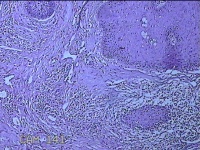

性别

男

年龄

45岁

临床诊断

皮下结节

一般病史

发现左侧一结节,伴局部瘙痒不适1年。

标本名称

左侧结节

大体所见

灰白暗红色带皮肤样结节0.8x0.7x0.3cm一个,表面糜烂,切开结节呈实性,切面灰白粉红色,质软。

感觉像表皮样囊肿?